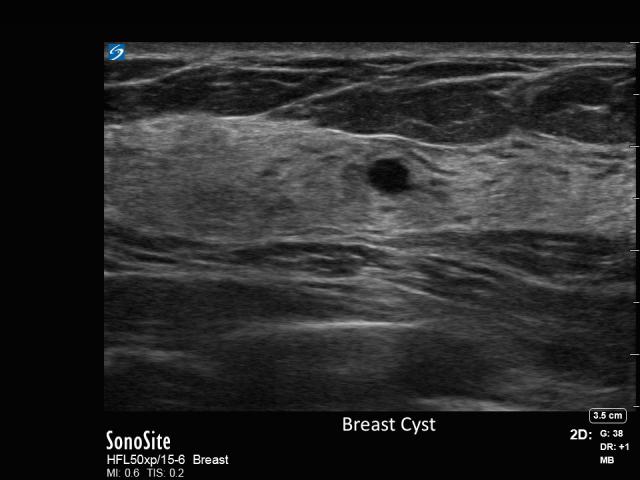

44-year-old female presents with “cord-like,” palpable lump on left breast.